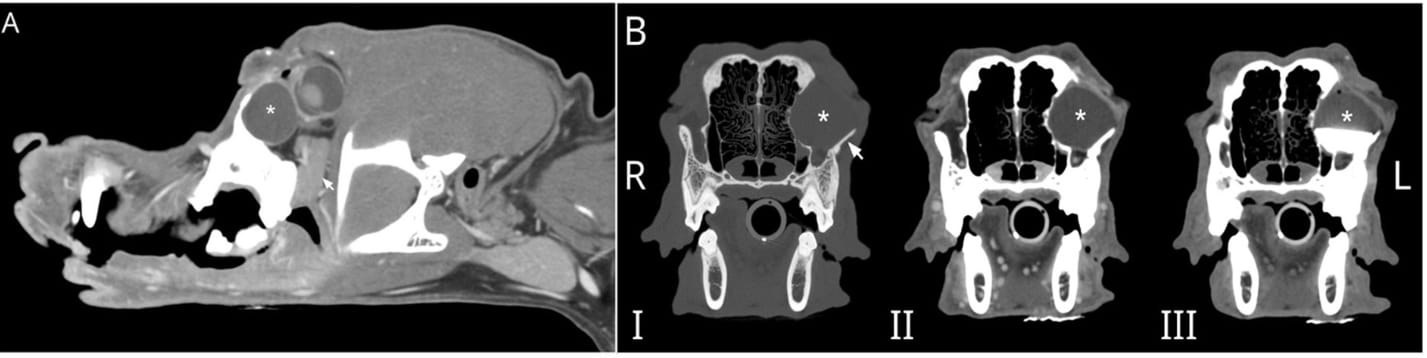

(A) Parasagittal reconstruction of the skull of a 10-year-old male castrated Golden Retriever post-IV contrast with a large, ovoid, fluid-filled structure (*) caudally displacing the globe. The zygomatic salivary gland (arrow) is ventral to the fluid-filled structure. (B) Multiphase transverse CT images show that this large, ovoid, fluid-filled structure (*) causes architectural changes to the left zygomatic arch (arrow). Dacrorhinocytography did not document contrast drainage into the intraorbital structure and did not drain into the adjacent canal (not shown) when contrast was directly injected into the structure in C. I- precontrast, II- post IV contrast, and III- post dacrorhinocytogram and direct injection into an ovoid fluid-filled structure.

A 10-year-old castrated male Golden Retriever presented with a 2-year history of a gradually enlarging intraorbital mass. CT imaging with contrast, including dacryocystography and direct lesion injection, was performed to evaluate the lesion’s structure and relationships. Cytology was performed following aspiration, and histopathology was conducted on tissue samples post-surgical excision via an intraoral approach. Follow-up CT imaging was performed four months post-operatively.

CT revealed a large, fluid-filled, non-communicating lesion displacing the left globe and causing remodeling of the zygomatic arch. Cytology suggested saliva with mild inflammation. Surgical removal yielded cystic tissue confirmed on histopathology to be salivary gland tissue with ductal structures, consistent with a diagnosis of salivary choristoma. A four-month postoperative CT showed a small remnant of the lesion, significantly reduced in volume (3.8% of original size), with no clinical signs warranting further surgery.